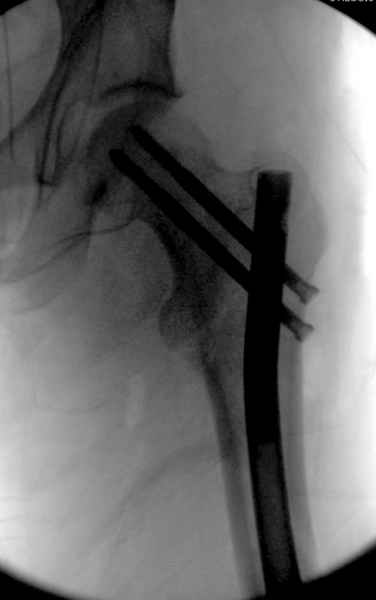

Как раз недавно у меня был примерный случай: больному 36 лет, поступил ночью, травма в результате мотоциклетной аварии, кроме чрезвертельного и спирального перелома левого бедра имеется переломы костей предплечья с этой же стороны. Скелетное вытяжение, а на следующий день больной про оперирован на ортопедическом столе с дистракцией. Чтобы не расколоть чрезвертельный перелом провели временную спицу ближе к переднему кортексу, из малого разреза костодержатель для репозиции, а фиксацию провели антиградным штифтом. Этапы операции на снимках.